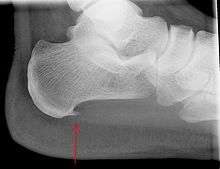

An incidental finding associated with this condition is a heel spur, a small bony calcification on the calcaneus (heel bone), which can be found in up to 50% of those with plantar fasciitis.[6] In such cases, it is the underlying plantar fasciitis that produces the heel pain, and not the spur itself.[12] The condition is responsible for the creation of the spur though the clinical significance of heel spurs in plantar fasciitis remains unclear.[11]

Medical imaging is not routinely needed as it is expensive and does not typically change how plantar fasciitis is managed.[13] When the diagnosis is not clinically apparent, lateral view x-rays of the ankle are the recommended imaging modality to assess for other causes of heel pain such as stress fractures or bone spur development.[7]